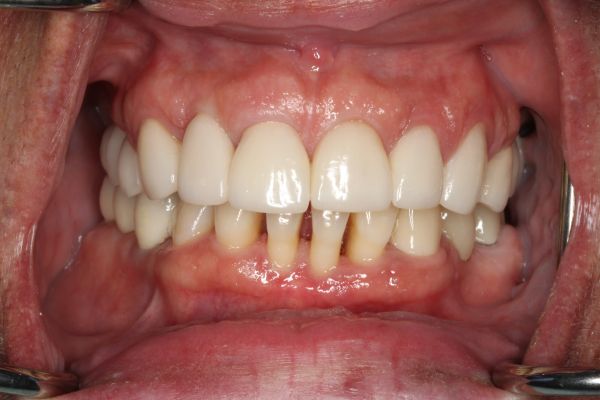

It’s never too late to restore and rejuvenate your smiles. After years of hiding her smile, this patient decided she had enough. With new upper and lower dental crowns and veneers on her front teeth, now she has the confidence to flash her pearly whites.

Crowns on upper front teeth 6-11 and lower front teeth 22-27 Crowns on the molars and bicuspids on the upper right and lower right. 3/4/5/28/29/30.

Crowns on lower front teeth 22-27.